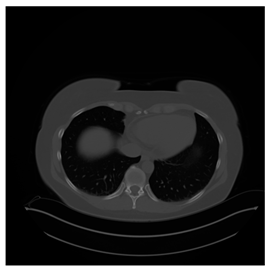

4.3. The Results

In this subsection, we describe three experiments used to measure the performance of the proposed method. The first experiment shows the stegoimage and marks the pixels’ positions that have been modified during the embedding process, as shown in Table 2, Table 3, Table 4, Table 5, Table 6 and Table 7. To make modified pixel positions have a pronounced effect, we set bpp (bit per pixel) rate at 0.05 and 0.025. It can be seen from the results that the proposed local complexity function can distinguish ROI and RONI from most of the medical images, so modified pixels are mainly gathered in RONI. However, it is observed that the proposed local complexity function cannot distinguish between ROI and RONI in the Prostate-MRI database due to the relative complexity of the image. Besides, “Modified BPP” represents the proportion of pixels in the image that have been modified. We observed that the performance of “baboon” in the grayscale standard images database is poor because that image’s pixels are relatively complex. It becomes challenging to select the more embeddable pixels based on the proposed local complexity function. Nevertheless, the modified pixel positions in other grayscale standard images, such as Lena and Barbara, are relatively smooth, verifying that our local complexity function is also applicable to general images.